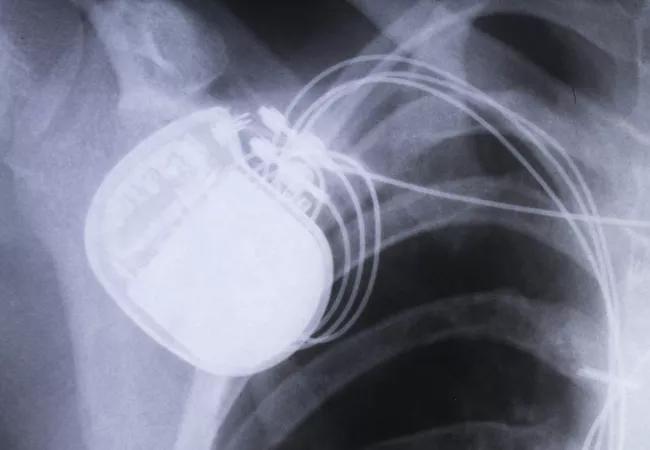

Despite common guidelines for cardiac resynchronization therapy (CRT) practice, the application of CRT differs substantially between U.S. and non-U.S. participants in the international Advance CRT Registry. And the differences suggest that patients receiving CRT in the U.S. are considerably more difficult to treat than their counterparts in other parts of the world.

The analysis also showed that U.S. patients were more likely to have a quadripolar LV lead implanted in the lateral location (P < .0001), whereas LV leads in non-U.S. patients were more likely to be bipolar and placed posterolaterally (P < .0001).

Although CRT defibrillators were used more widely than CRT pacemakers in both groups, the proportion of defibrillator use was greater among U.S. patients (P < .001).